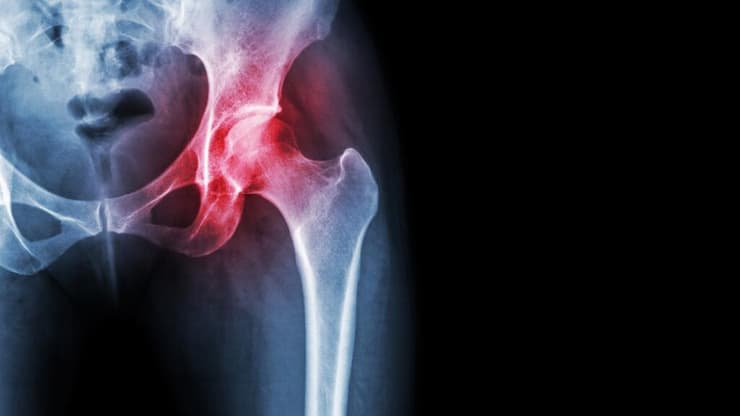

ניתוח החלפת מפרק ירך הוא אחד הניתוחים הפופולריים ביותר בתחום האורתופדיה. עד לא מזמן, ניתוח זה נעשה כמעט באופן בלעדי באנשים מבוגרים, בעיקר אחרי גיל 60. אך היום התמונה השתנתה, והיא ככל הנראה תמשיך להשתנות גם בשנים הקרובות. מחקרים מהשנים האחרונות מצביעים על מגמת ירידה בגיל המנותחים, ויותר חולים צעירים עוברים ניתוח החלפת ירך.

את הירידה בגיל המטופלים שעוברים ניתוח להחלפת הירך ניתן להסביר בכמה דרכים. הסיבה המובילה להחלפת ירך היא שחיקת סחוס (אוסטאוארטריטיס), גם בגיל השלישי וגם בקרב בני 40 עד 50. שחיקת סחוס ראשונית לרוב מתרחשת עם הגיל, אולם צעירים יכולים לסבול משינויים ניווניים משניים שיצריכו החלפת מפרק הירך בשלב מוקדם יותר מהרגיל. צפו בהצצה קצרה לניתוח:

ניתוח החלפת מפרק ירך

(צילום: אלי דדון)